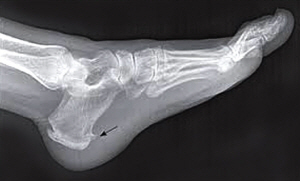

족저근막염 부위

족저근막염 부위 /자료=연세건우병원

족저근막염 증상